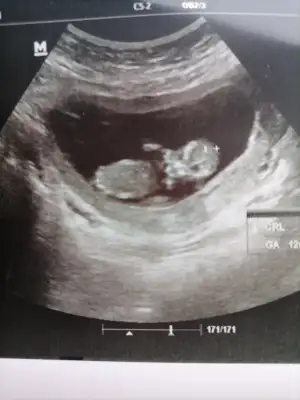

Bence kiz bugün bende kontrole gittim 11+3 kiz diye tahmin etti kesin olmamakla beraber görüntü böyleTahminlerini bekliyorum![]()

Ay inşallh kız istyorum sen ne istyorsun canımBence kiz bugün bende kontrole gittim 11+3 kiz diye tahmin etti kesin olmamakla beraber görüntü böyle